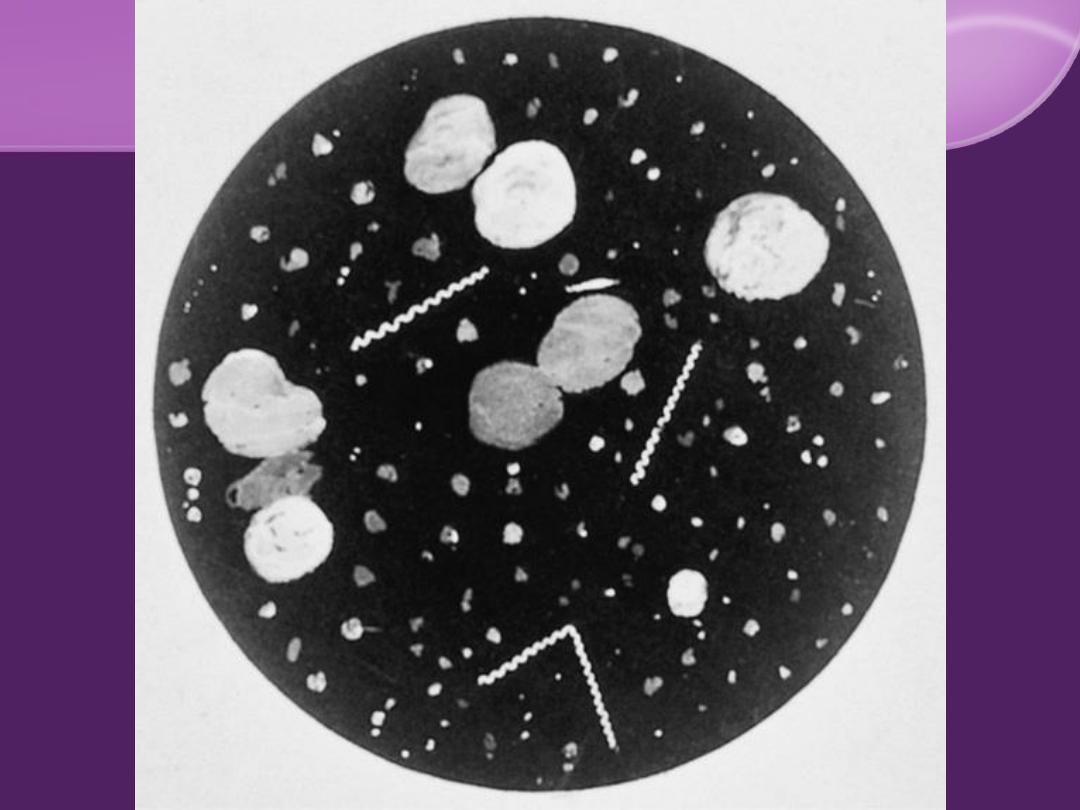

Microbiology:

T. pallidum

Spiral bacterium (spirochete)

Corkscrew rotation motility

Dark Field M

Non culturable